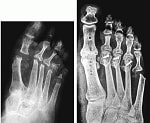

●行われる部位

上半身ではひじ下半身ではひざと股でよく行われ治療成績もすぐれています。

固定術・形成術

関節固定術

関節形成術

腱の形成術